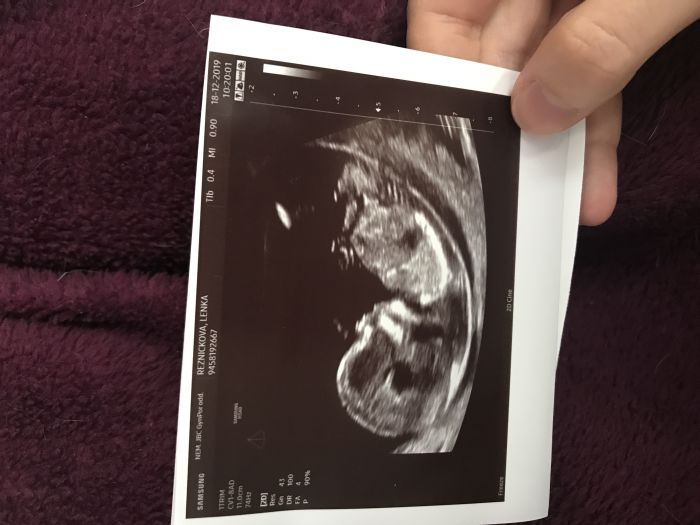

Ahojky, hlásím, že včerejší screening dopadl na jedničku:)) Dokonce paní doktorka už hematom nikde nenašla, takže snad už je to vše za námi a můžeme se pořádně začít těšit na další miminko:) Už nám chtěla hlásit pohlaví, ale odolali jsme, bude překvapeni:). Jediné co, tak mám vyšší riziko preeklampsie, ale myslím si, že se mě to nakonec týkat nebude, jediné, co k tomu MUDr. vedlo byl větší odpor cév na levé straně, tlak mám klasicky nízký, tak snad bude tohle bezpředmětné, budu ale brát pro jistotu celé těhotenství nějaké léky. Posílám fotku toho našeho broučka, dcera říká, že brášky:D A přeji vám všem krásné Vánoce, ať jsou jen samé pozitivní reakce pro ty, co si oznámení těhotenství nechávají pod stromeček:)